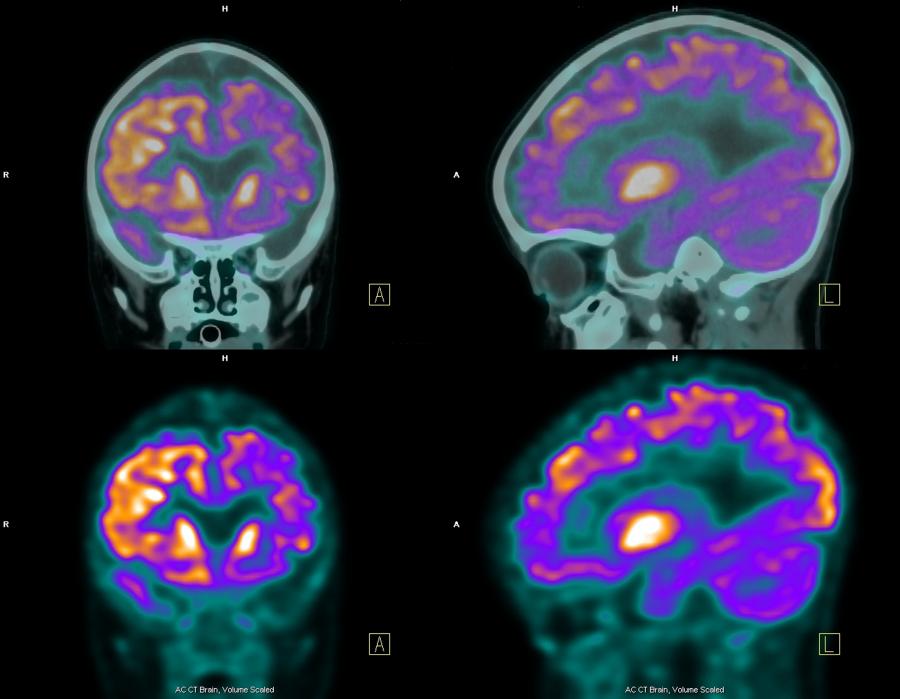

ANSTO has the expertise and capabilities to supply radioisotopes and undertake characterisation, radiation biology and preclinical imaging studies to develop and evaluate radiopharmaceuticals.

ANSTO was part of an Australian biopharmaceutical collaboration that developed an innovative cancer diagnostic agent, which can be used to detect and potentially monitor metastatic prostate, bladder and pancreatic cancers using SPECT/CT.

Health researchers design and optimise treatment tools and methods using nuclear techniques, model complex radiation physics and use nuclear techniques to understanding the neurophysiology of the brain and characterising key processes and pathologies.